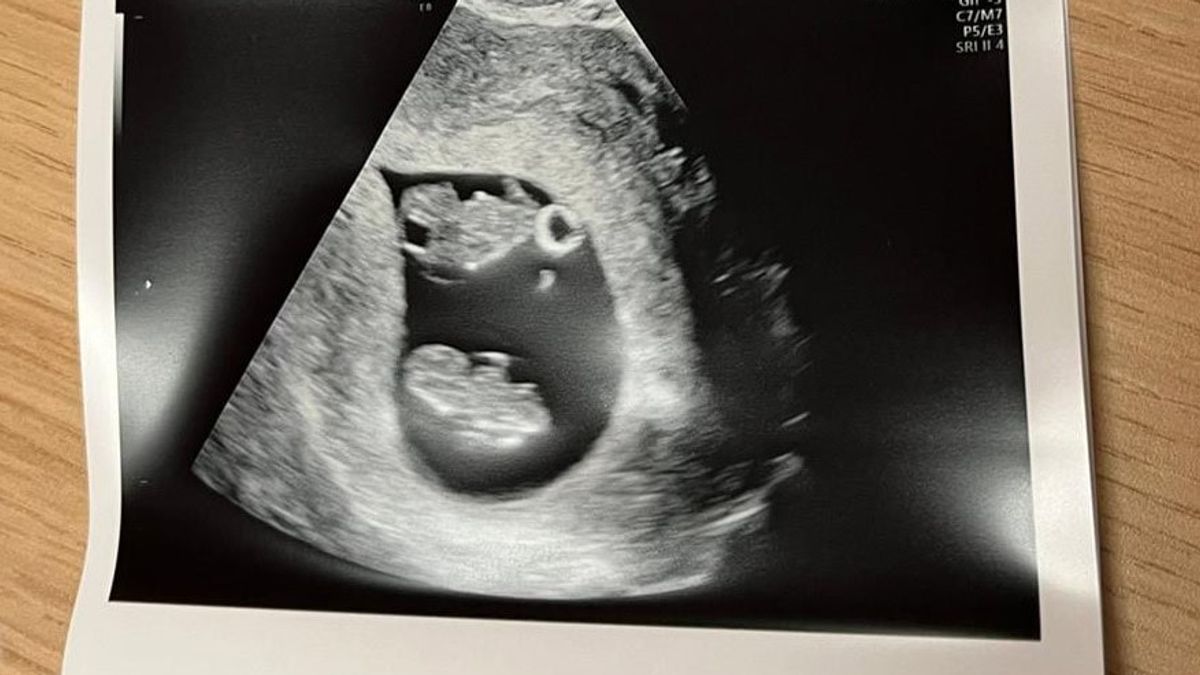

Meike: “We hadden niet eens tijd om het beeld van een tweeling te verwerken, toen we het slechte nieuws kregen. Ik had geen hoop meer op een goede afloop. De echoscopist zei: “jullie hebben nog een lange weg te gaan”

Ik zal niet de spanning opbouwen tot de volgende blog en de cliffhanger nu vast verklappen. Vier dagen later hadden we een uitgebreide echo in het ziekenhuis waar gelukkig geconstateerd werd dat ze wel allebei een eigen vruchtzak hebben, maar wel de placenta moeten delen (MCDA). Ik kan je wel vertellen dat door deze enorme rollercoaster en angst in deze paar dagen, er niet eens ruimte is geweest om het nieuws en de schok van überhaupt 2 baby’s ruimte te geven.